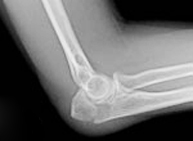

La articulación del codo está formada por las porciones inferior del húmero y superiores de cúbito y radio. Su lesión se produce fundamentalmente tras el impacto de la mano contra el suelo con el codo en extensión, siendo especialmente vulnerables los niños y la tercera edad. Tanto si existe rotura ósea (fractura) como si hay separación entre los huesos de la articulación (luxación) se requiere un diagnóstico eficaz y un rápido tratamiento para evitar la aparición de secuelas.

La paleta humeral es la porción inferior del húmero que conecta con la parte superior del cúbito y radio formando la articulación del codo. Los traumatismos en esta región suelen producirse tras caída e impacto sobre la mano con el codo en extensión. Es necesaria una exploración neurovascular urgente para valorar lesiones en estructuras vasculares y nerviosas que pasan a este nivel y que se encargan del trofismo de la mano. El tratamiento se realizará en función del tipo de fractura y la edad del paciente con la finalidad de restituir, lo antes posible y sin secuelas, la funcionalidad de la articulación del codo.

Las fracturas de radio son producidas fundamentalmente de forma indirecta por transmisión de un impacto de la mano hacia el codo. Pueden ser caídas fortuitas o durante la realización de actividad deportiva o laboral. Cuando tienen lugar el codo se inflama y su movimiento es muy doloroso. El tratamiento busca la restitución de la anatomía normal del radio para iniciar el movimiento cuanto antes e impedir la aparición de rigidez.

El olécranon es la parte superior del cúbito que articula con el húmero para que podamos realizar la flexión y extensión de nuestro codo. Una fractura de olécranon supone la imposibilidad para la realización de esta función. Ocurren tanto en el paciente de edad avanzada como en el joven y suele ser por caídas con el codo en flexión. Dada su relevancia en el movimiento del brazo su reparación debe ser rápida y precisa para evitar secuelas en la bisagra del codo. A través de procedimientos mínimamente invasivos se puede conseguir la restitución articular minimizando los riesgos de grandes cirugías e iniciar el movimiento en un breve período de tiempo.